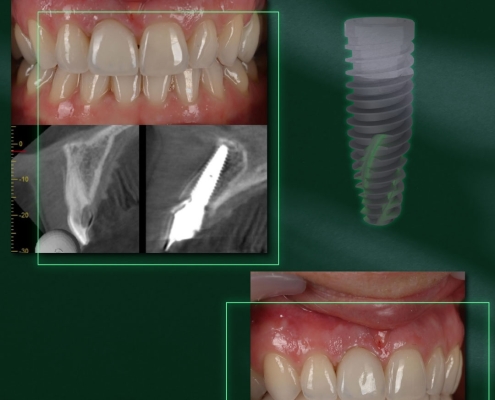

Cas clinique : Pose à main levée d’un implant SP1 3.5 x 10 mm

Ce cas illustre la mise en place d’un implant SP1 dans le secteur antérieur, avec un objectif esthétique exigeant et une intégration prothétique parfaitement naturelle.

Ce cas illustre la mise en place d’un implant SP1 dans le secteur antérieur, avec un objectif esthétique exigeant et une intégration prothétique parfaitement naturelle

La planification préopératoire a permis de positionner l’implant selon un axe optimal, garantissant à la fois une émergence prothétique idéale et une préservation tissulaire.

L’implant SP1 (3.5 mm) a été choisi pour sa connexion unique et sa géométrie compacte, facilitant la gestion des espaces interdentaires tout en offrant une stabilité primaire remarquable.

La phase prothétique met en évidence la cohérence du concept Single Platform One : un seul diamètre de connexion pour l’ensemble de la gamme, simplifiant le travail conjoint du praticien et du laboratoire.

La restauration finale s’intègre parfaitement à l’arcade, avec une harmonie gingivale et esthétique qui témoigne de la précision de l’ajustement et de la biocompatibilité des composants.

Implant : SP1 3.5 x 10 mm

Protocole : Pose à main levée